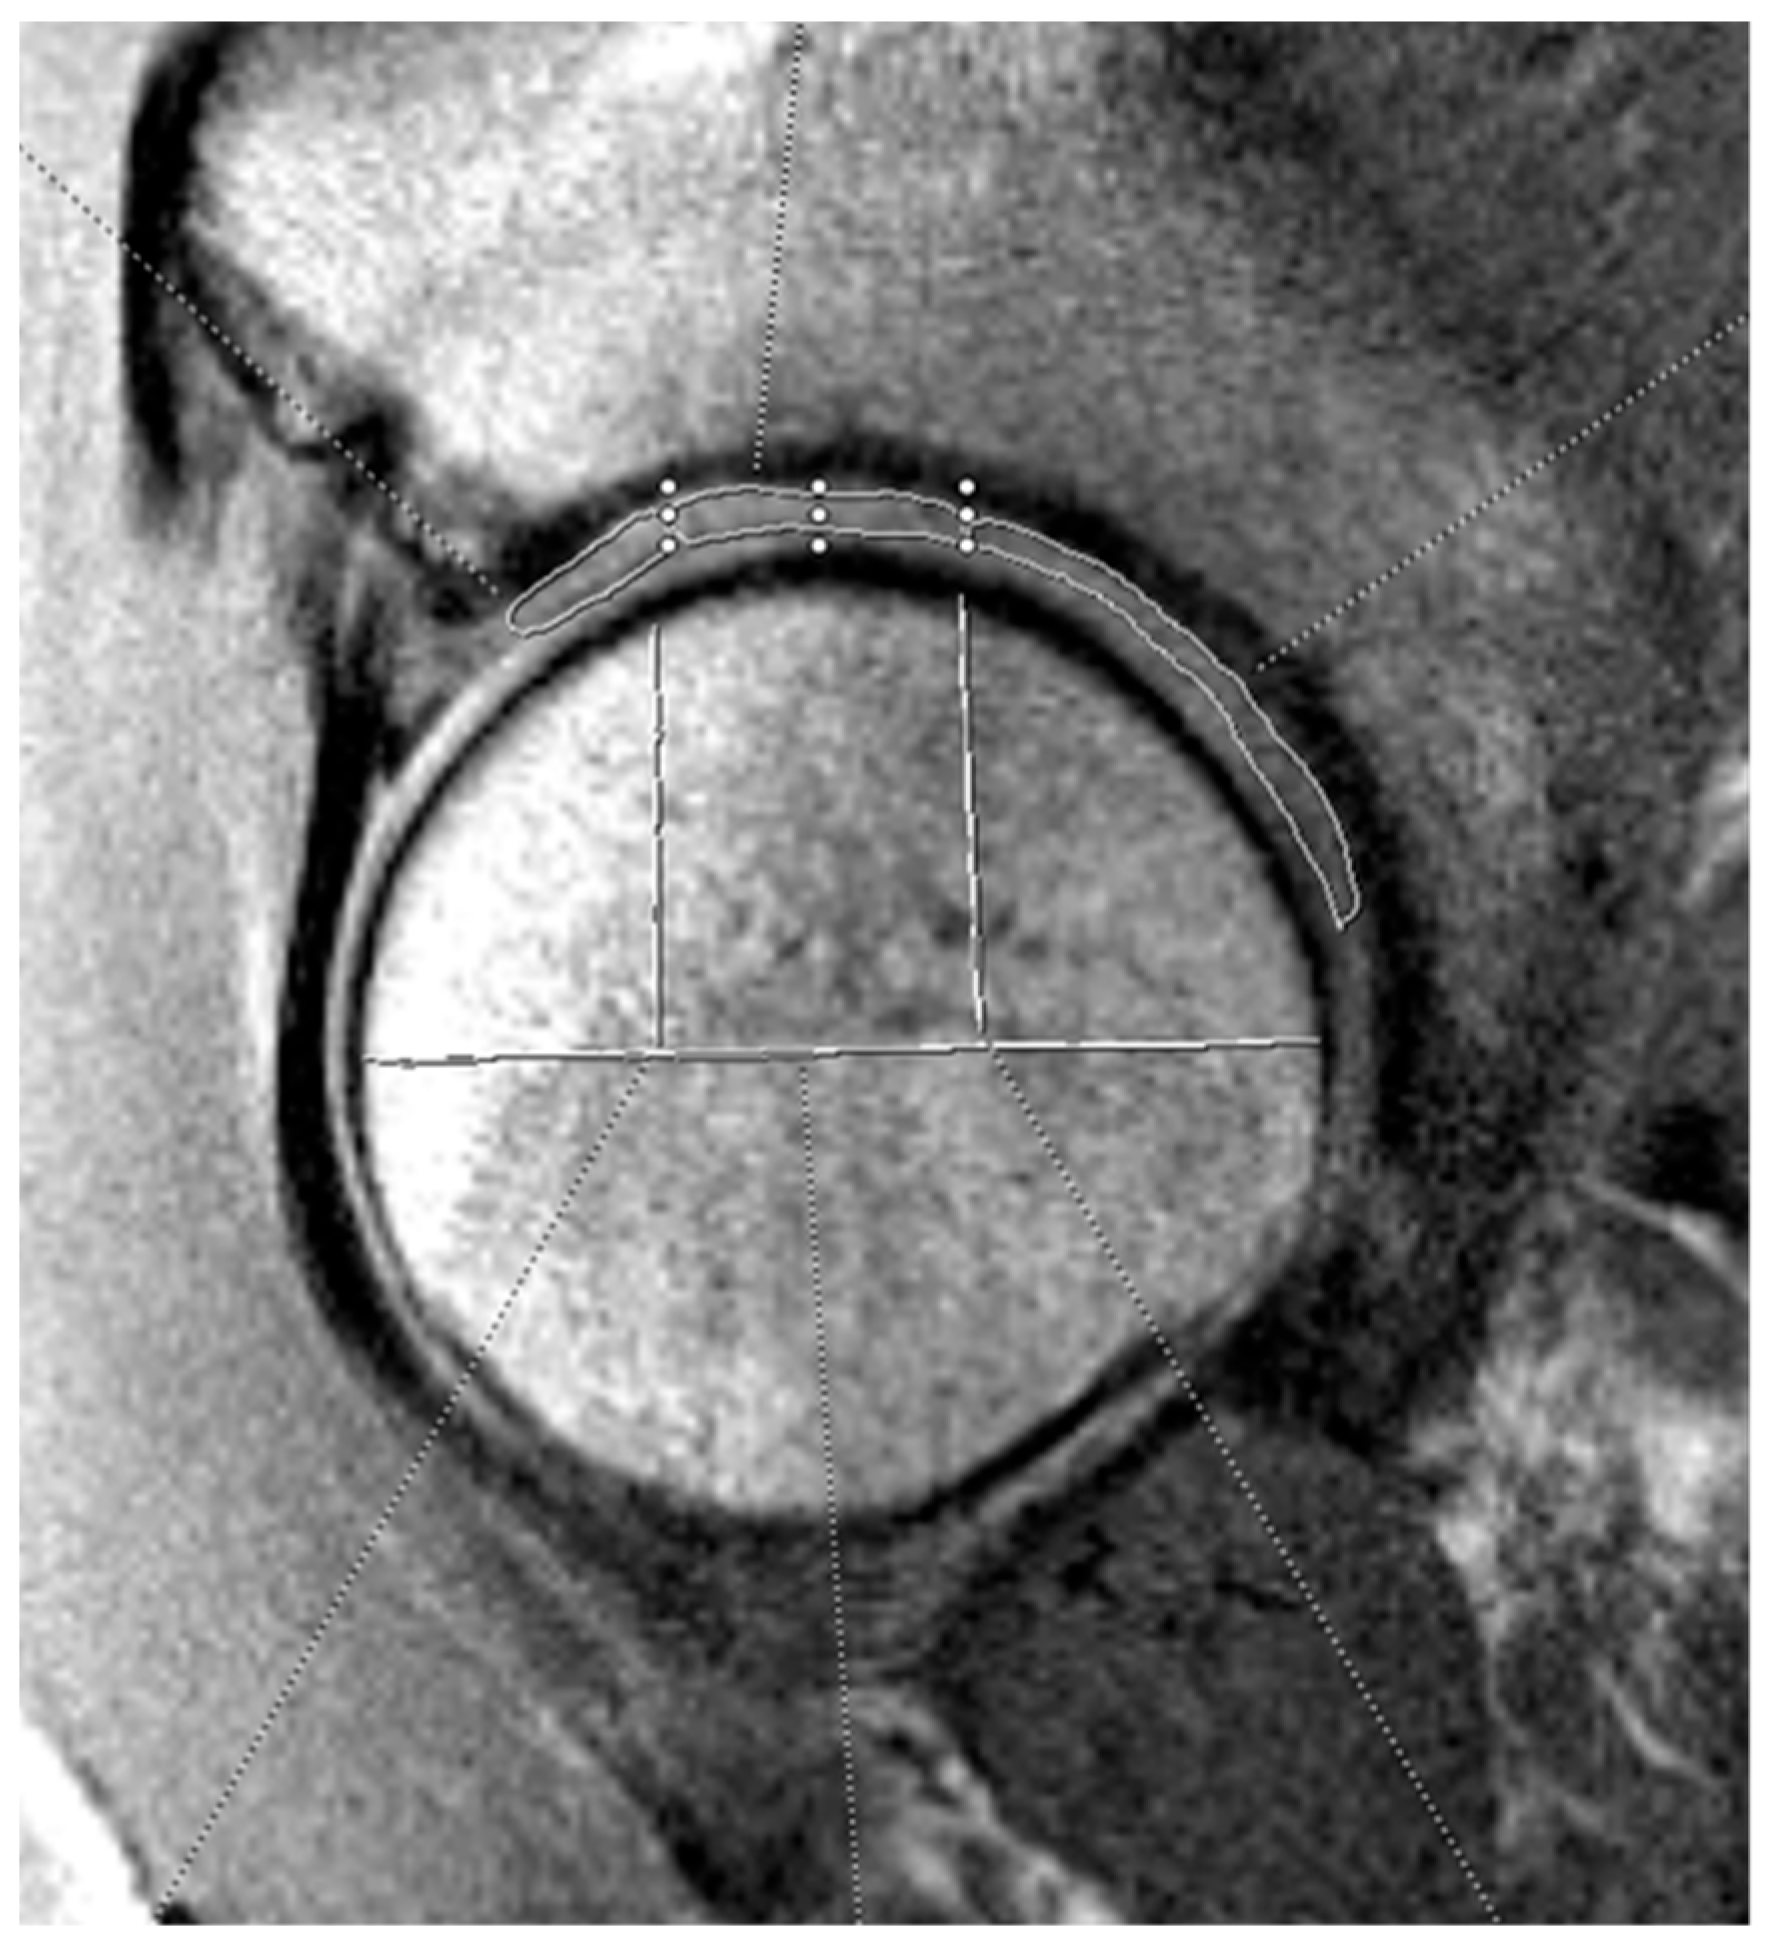

The three independent, blinded reviewers analyzed T2 mapping on the optimal sagittal MRI cut using the Syngo.via T2 mapping software (Siemens Healthineers, Erlangen, Germany). Reviewers included an orthopedic surgery resident (A.P.) and two medical students (C.A., K.J.) supervised by a board-certified musculoskeletal radiologist (C.H.). For T2 analysis, the acetabular and femoral head cartilage were each divided into anterior, superior, and posterior zones. See Figure 1 and Figure 2 for a visual representation of this division in the mapping software. The average T2 mapping value for each respective zone on the acetabulum and femoral head were measured two times by each of the three reviewers and the average of these values was taken. Intraclass correlation values were obtained to confirm appropriate inter-observer agreement. Hip morphology measurements were recorded from CT scans using 3D reconstruction and measurement software (HipMap, Stryker, Kalamazoo, MI, USA). Measurements included alpha angle, lateral central edge angle (LCEA), acetabular coverage, femoral version, acetabular version at 12 o’clock, 2 o’clock, and 3 o’clock, femoral neck-shaft angle (FNSA), and Tönnis angle.

Figure 1. Example of acetabular cartilage T2 mapping on a sagittal MRI. The measurements were divided into three zones (anterior, superior, and posterior). The horizontal white line bisects the femoral head, and the vertical lines split the joint surface into 3 zones: anterior (left), superior (middle), and posterior (right). The three zones on the acetabular cartilage are drawn by free-hand technique based on these divisions.